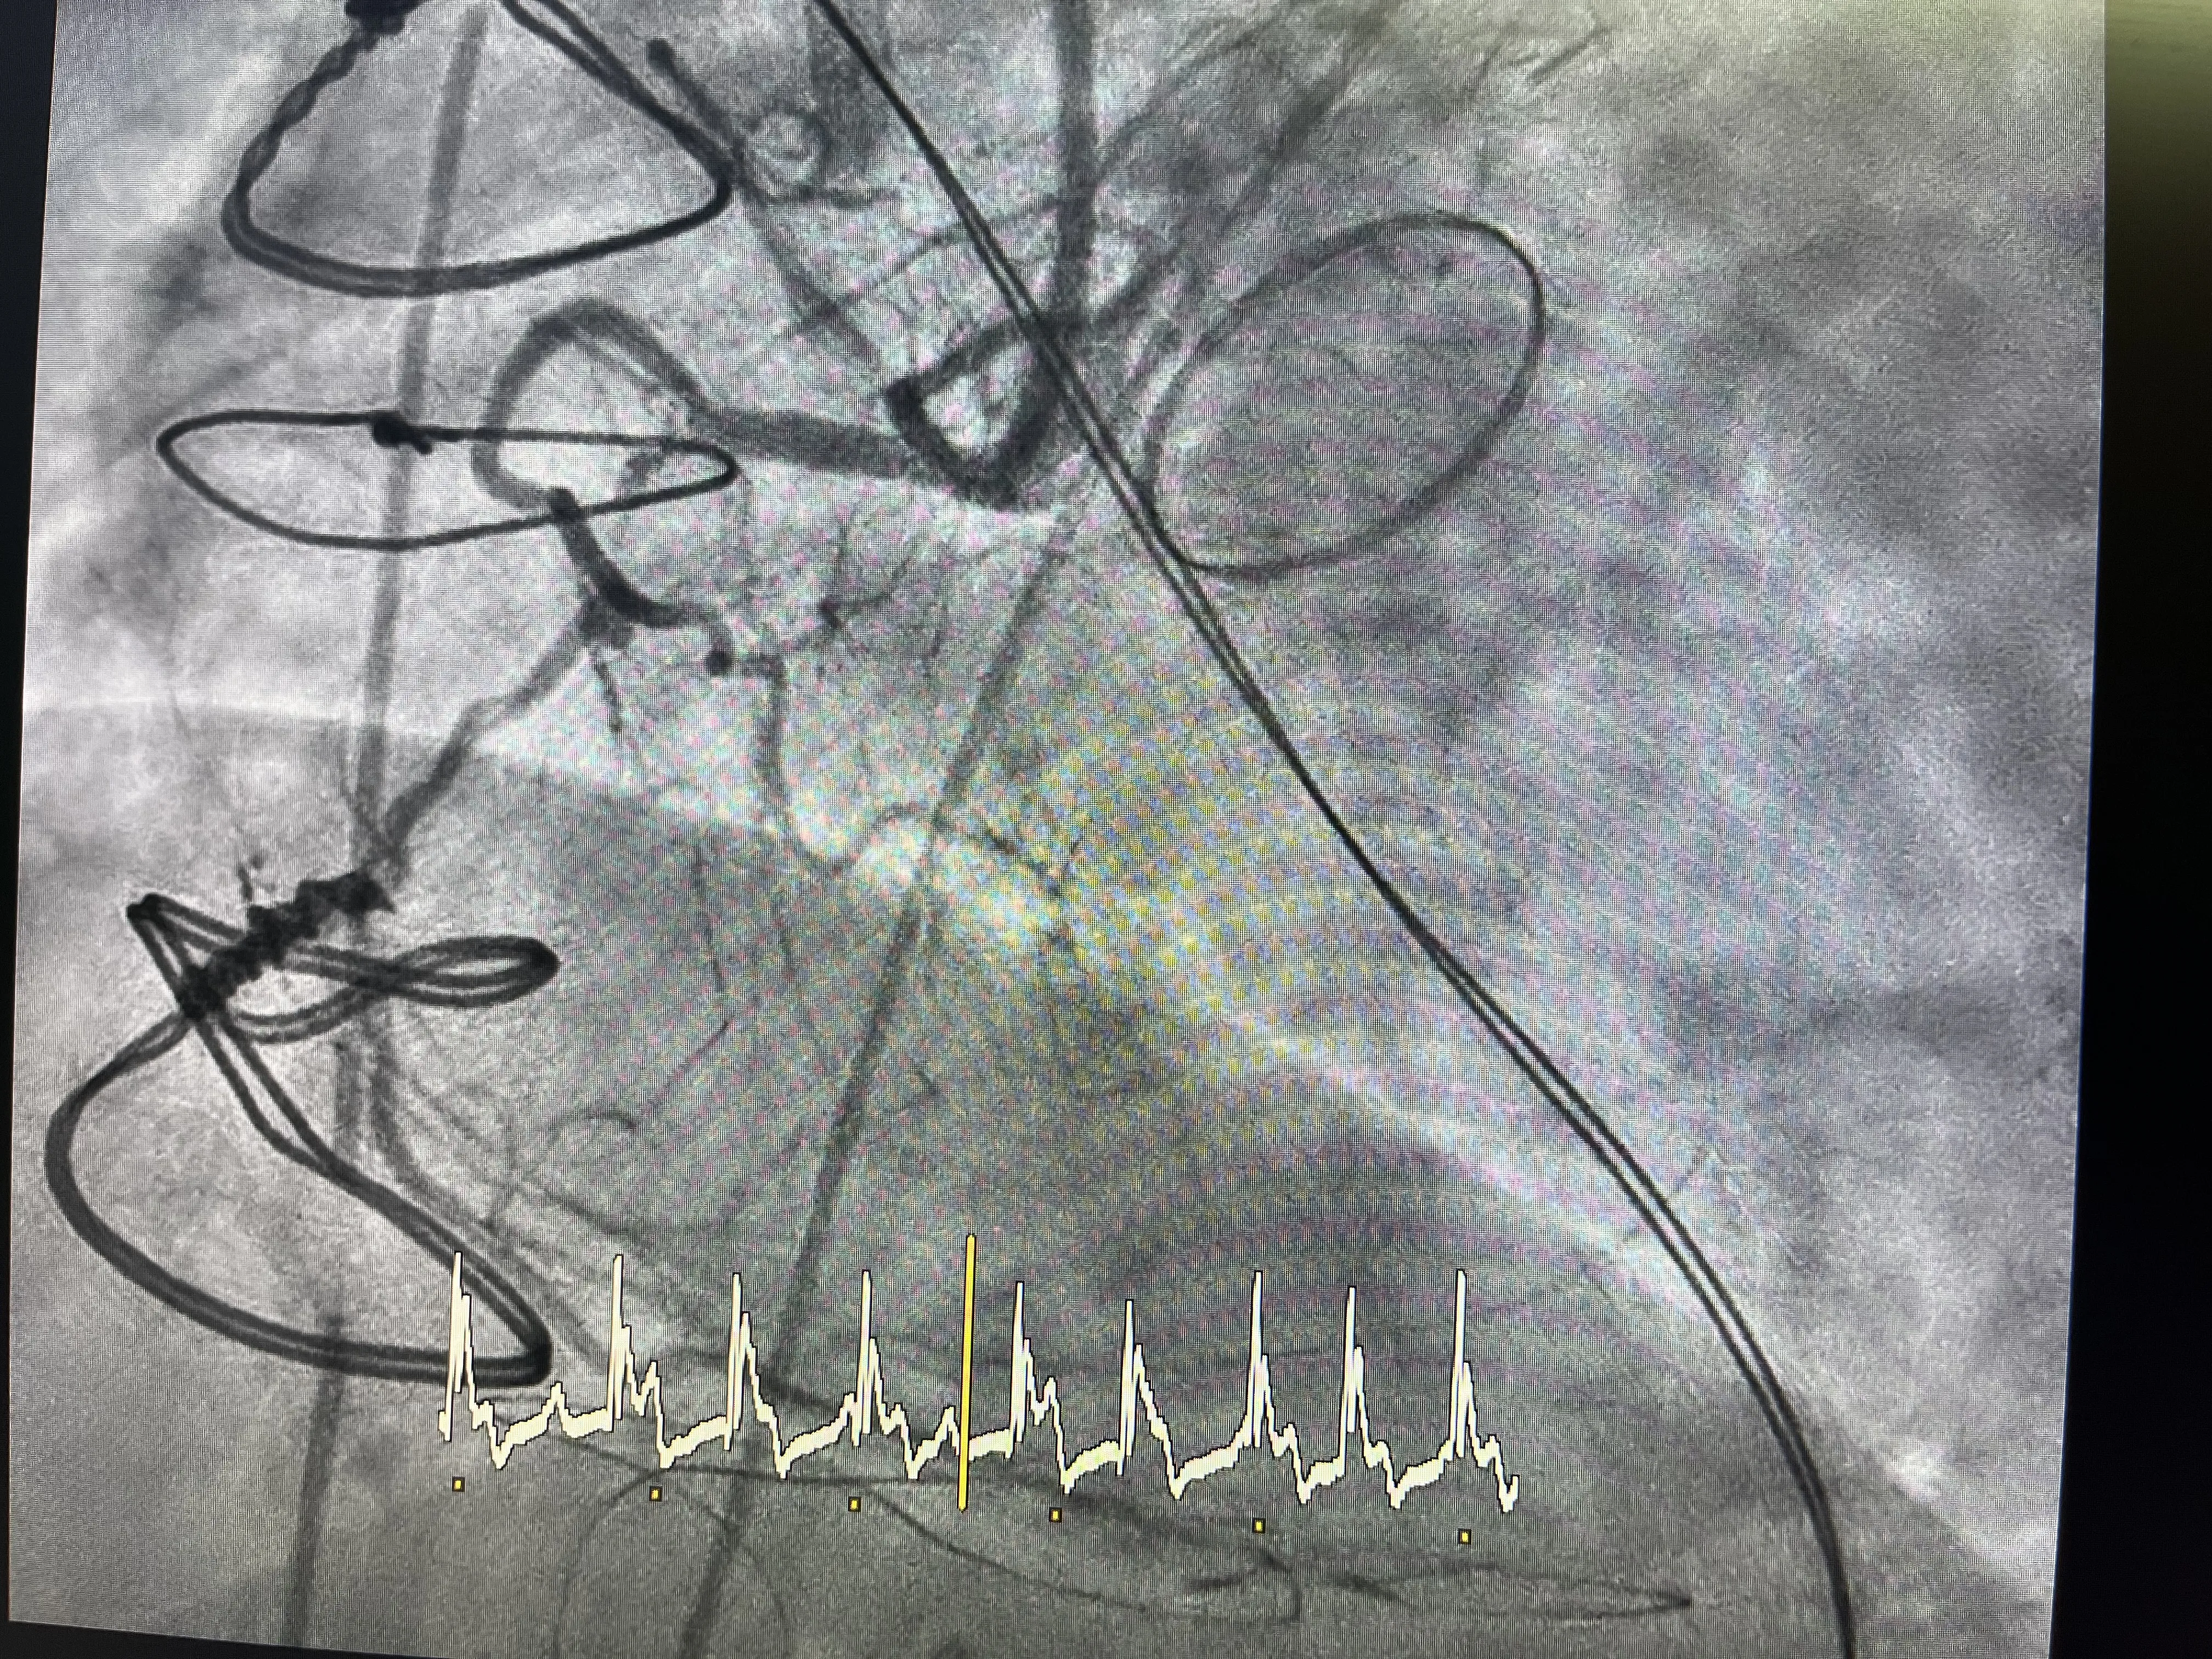

Predilatación y Colocación de Stent

Una vez identificada la oclusión de la circunfleja, el siguiente paso es intentar abrir la arteria con un balón. Se realiza una predilatación cuidadosa, avanzando un balón a través de la zona donde la arteria ha quedado comprometida por la sutura de la válvula mecánica. Esta maniobra busca crear un lumen mínimo que permita restablecer parcialmente el flujo y valorar la respuesta del territorio distal. Es un momento crítico, porque se está actuando en una zona anatómicamente compleja y recientemente manipulada quirúrgicamente.

Tras la predilatación, se observa una mejoría en el paso de contraste, lo que indica que la arteria puede mantenerse abierta si se le da un soporte estructural. En ese punto se decide implantar un stent en la circunfleja, con el objetivo de mantener el vaso expandido y evitar una nueva oclusión. La colocación del stent en este contexto no solo trata una estenosis, sino que compensa el efecto de la sutura que había estrangulado la arteria. Es una solución percutánea a una complicación mecánica generada en quirófano.